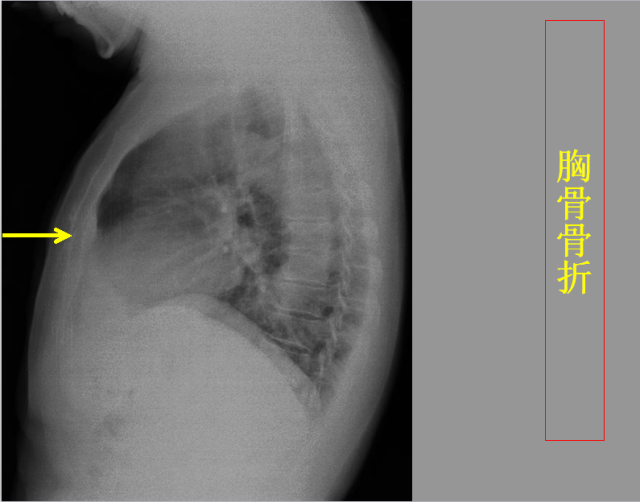

急胸症篇